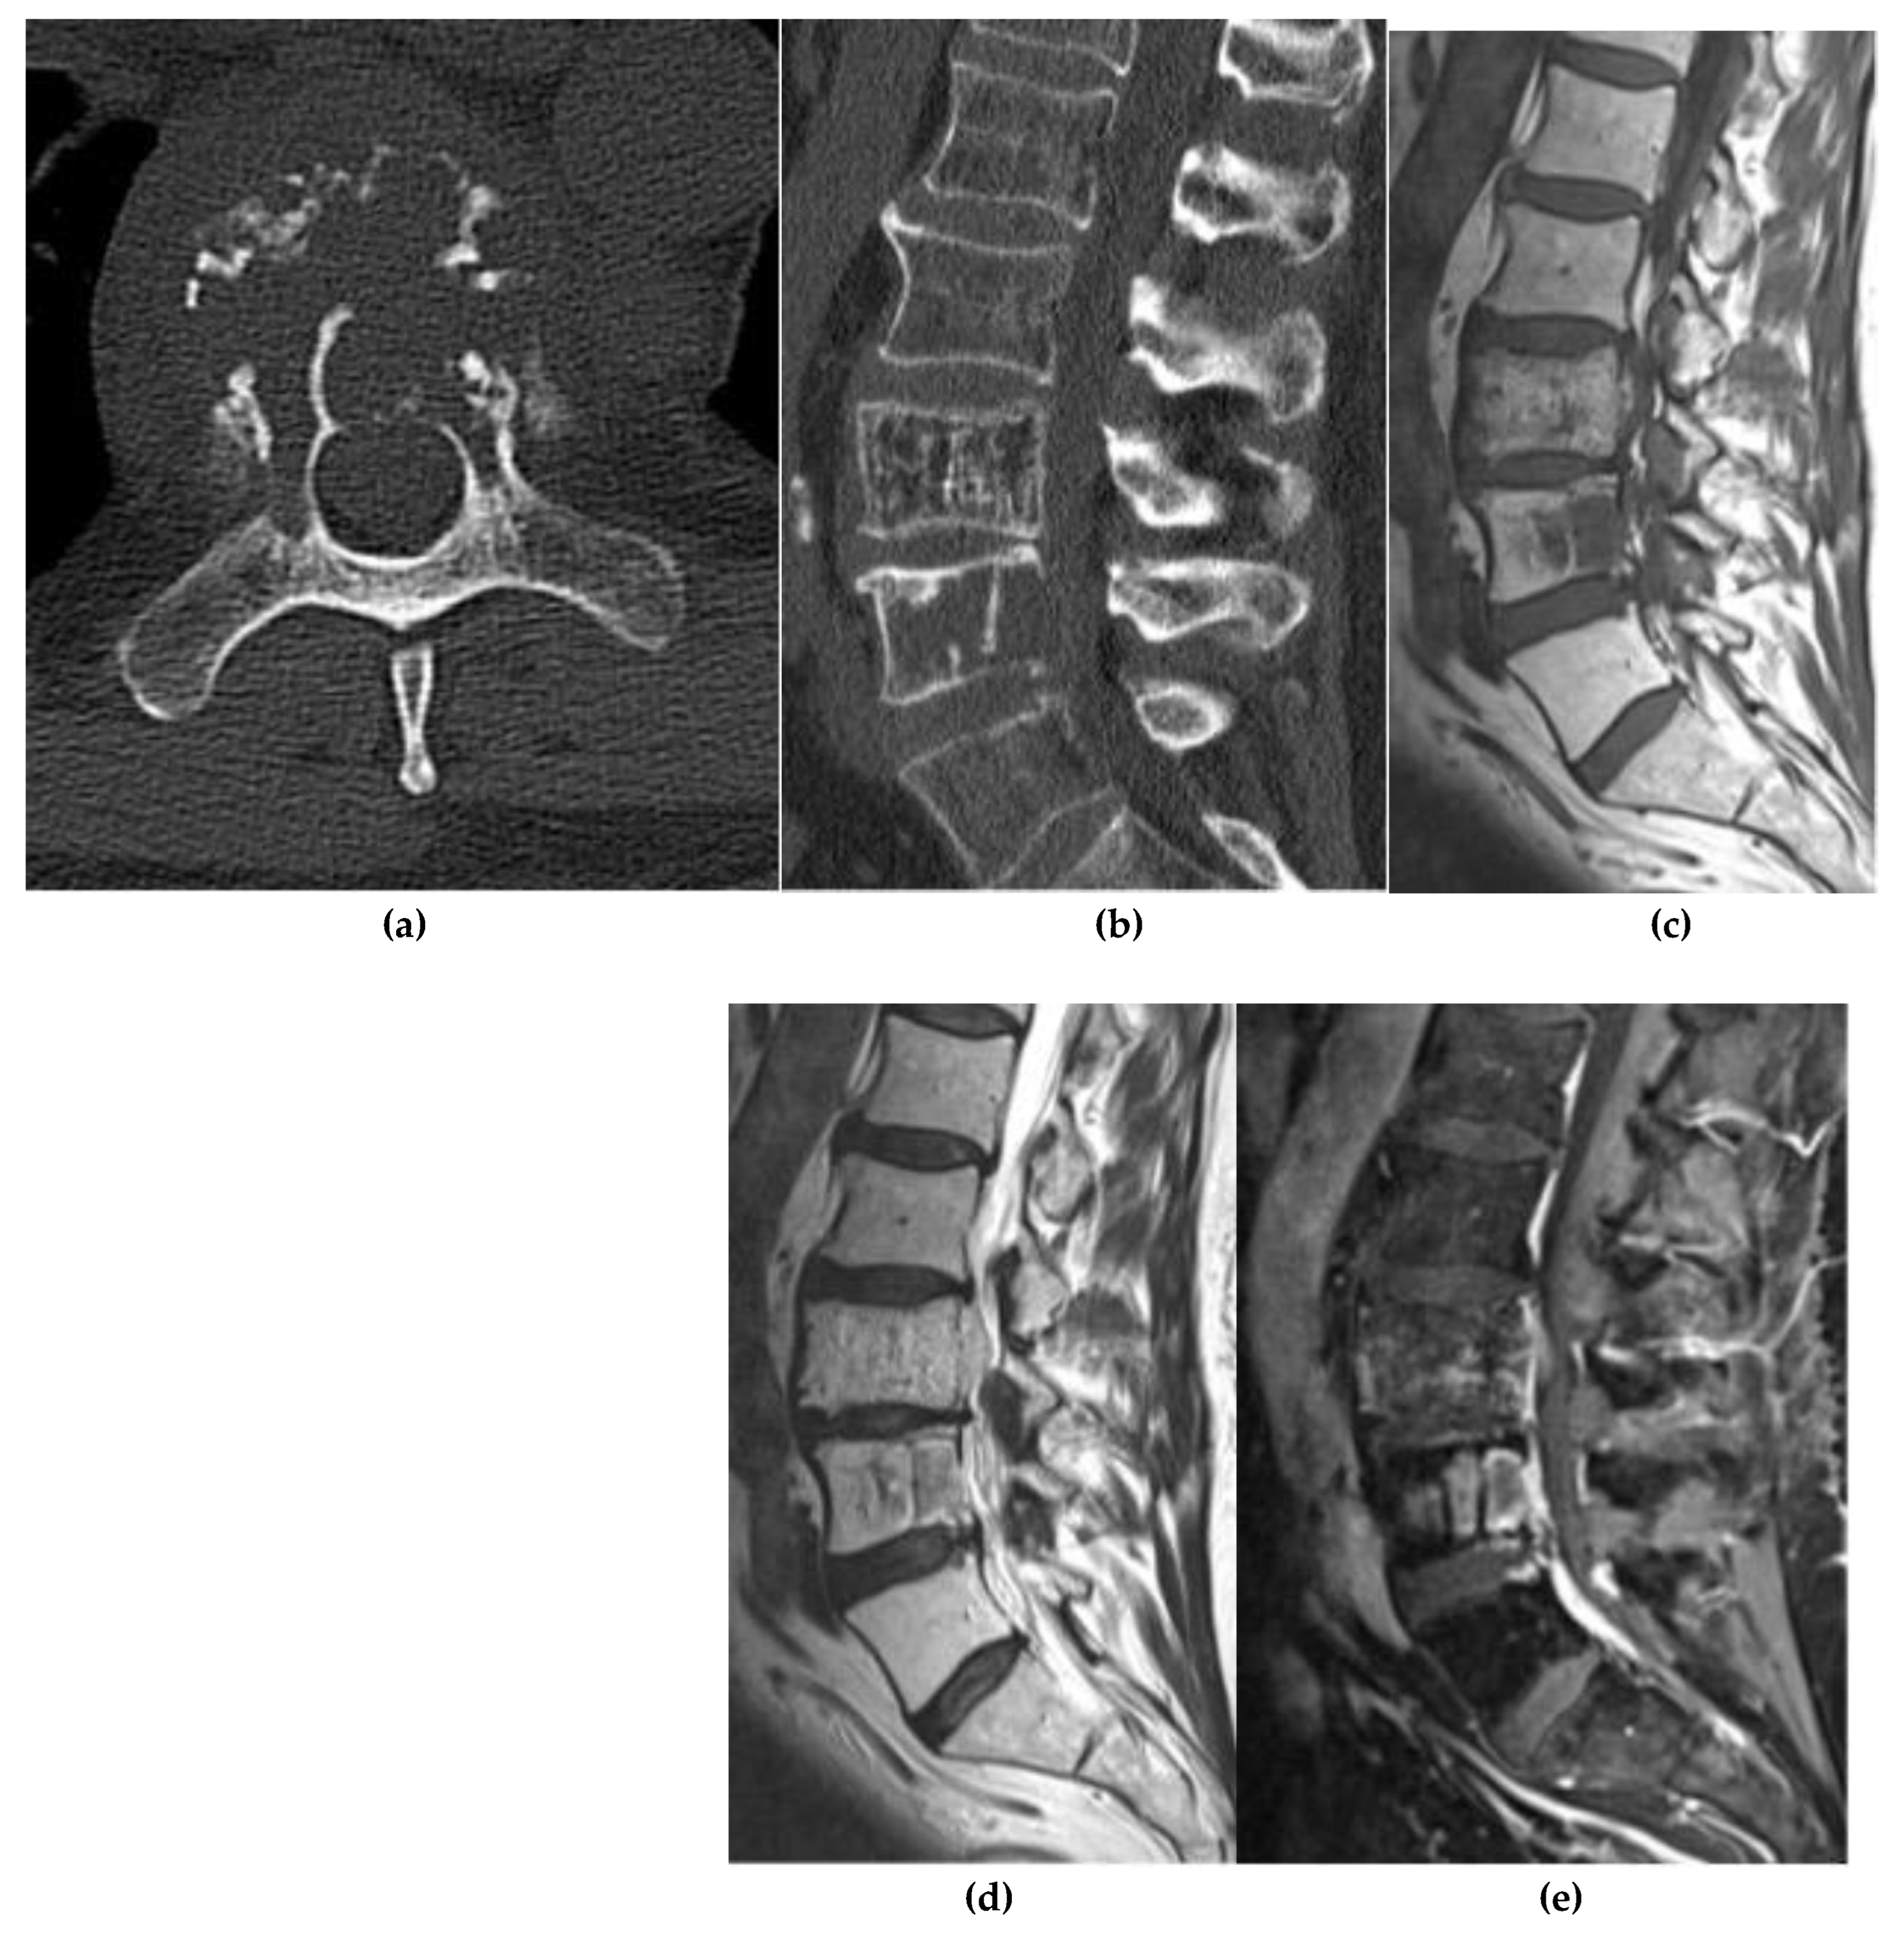

Osteoblastoma

Osteosarcoma

- Liu, J. , Han, S., Li, J., et al. Spinal Osteoblastoma: A Retrospective Study of 35 Patients’ Imaging Findings With an Emphasis on MRI. Insights Imaging 2020, 11, 122. [Google Scholar] [CrossRef]

- Huang, Z. , Fang, T., Si, Z., et al. Imaging Algorithm and Multimodality Evaluation of Spinal Osteoblastoma. BMC Musculoskelet. Disord. 2020, 21, 240. [Google Scholar] [CrossRef]